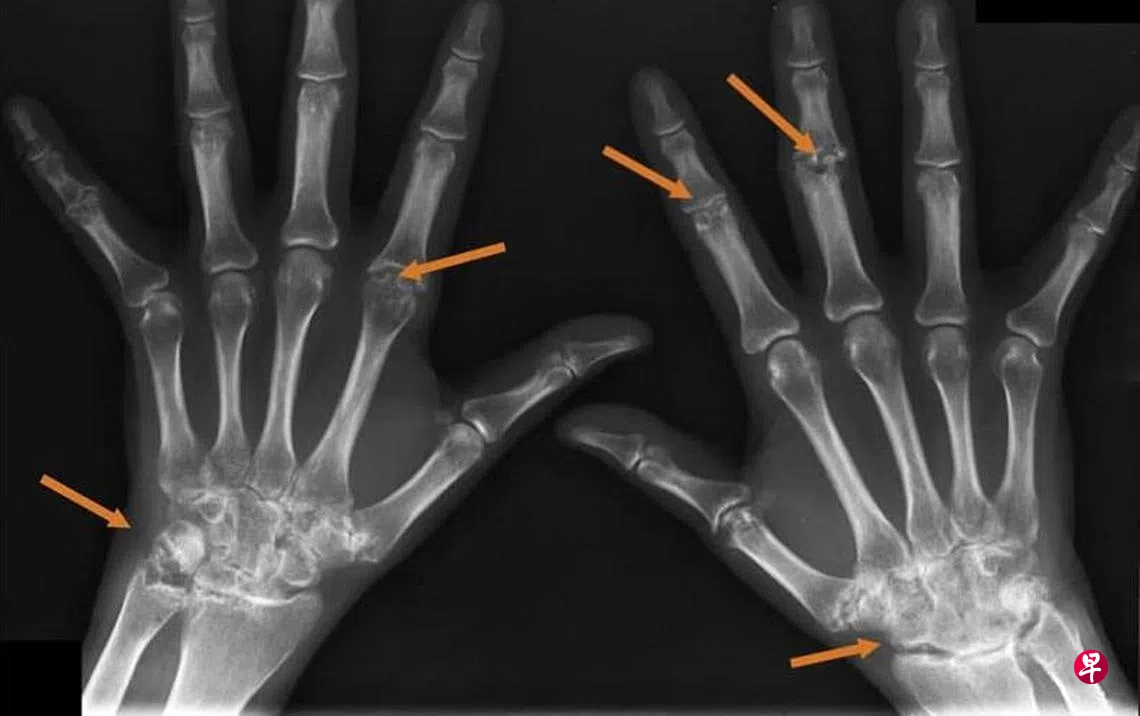

亚历山大医院慢性疾病科主任兼风湿免疫科高级顾问医生陈锦仪接受《活得好》访问时说,医生多数依靠详细的病史采集和身体检查,并通过验血和X光,以诊断是否患风湿性关节炎。

如果关节肿胀,尤其是膝盖,可能需通过针穿活检,抽取关节液的样本进行检验。检验结果可帮助医生区分关节病是属于传染性、退化还是炎症。